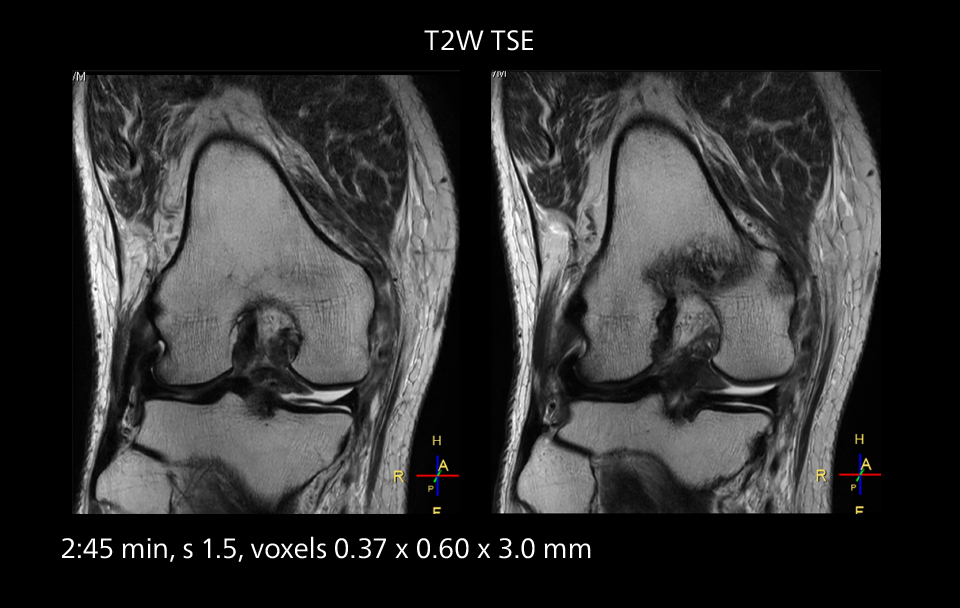

MRI of the knee

Images showing a posterior cruciate ligament (PCL) tear, a detached medial collateral ligament (MCL) on the tibial side and an intact anterior cruciate ligament (ACL). SmartPath to Elition X helped reduce scan time compared to previous imaging while maintaining resolution.

An example of increased imaging speed is in knee studies. “There is a definite scan time reduction for T2* mFFE and proton density TSE – both of these sequences benefit from much shorter repetition times,” he reports.

Overall, imaging time per sequence has been reduced since the Elition X upgrade. This can help reduce the risk of patient movement and the need for rescans.